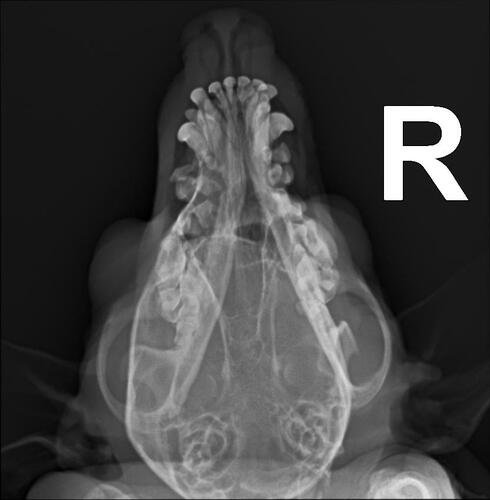

Eu sou Adriana tutora cadelinha Pirradia, que fOi atacada por um Pit Bul e está com fragmento ósseo da fratura nasal, visto após Ex de RX com laudo.

Valor da cirugia 2.500,00 a 3.000,00.